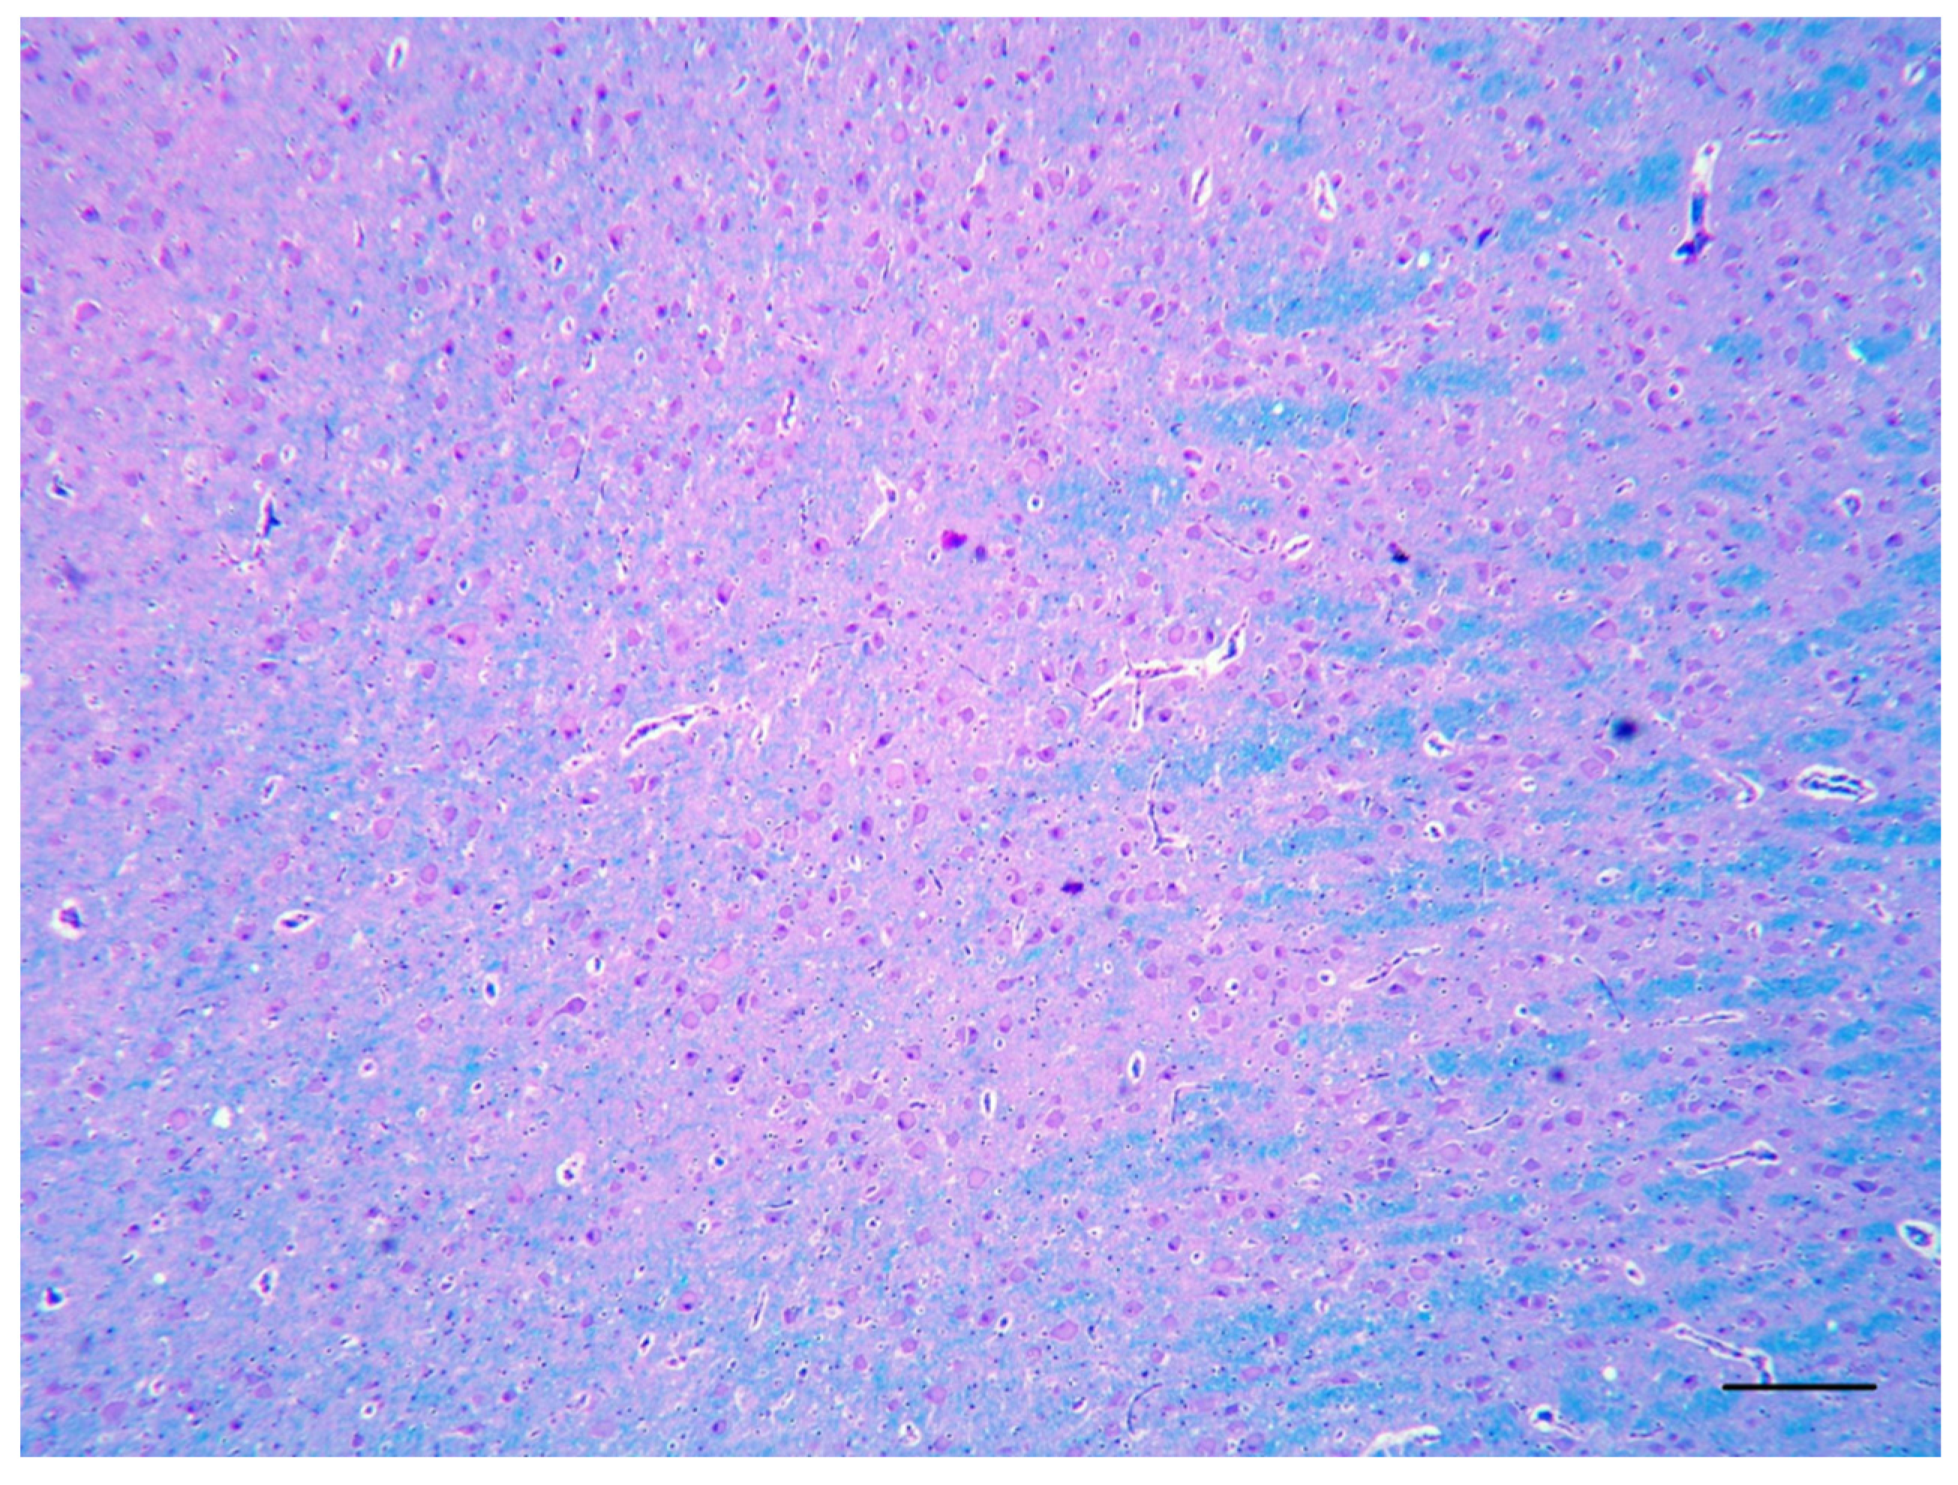

2. Case Description